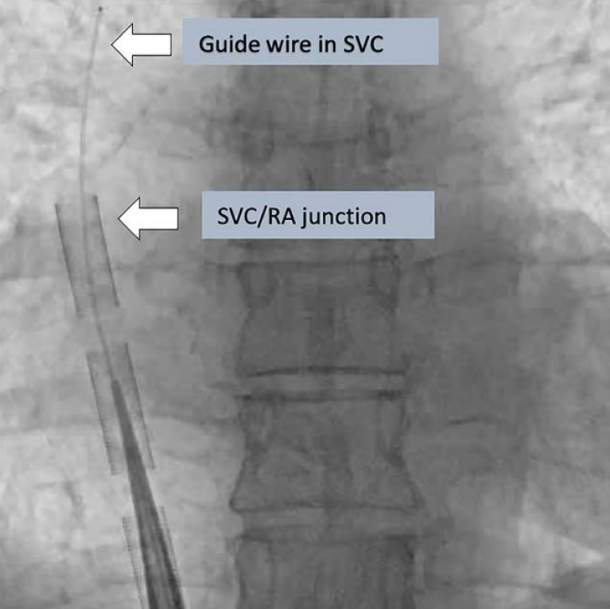

在给予足够抗凝治疗后,在相应的血管中置入标准导丝,并进行逐步扩张以便于置入插管。在某些情况下,如肥胖、解剖结构扭曲和周围血管疾病,可能需要硬导丝支撑,然后将插管分别置入股动脉和静脉。推荐使用影像(超声,x线透视或x线片)来确认导丝的初始位置,引引导丝前进,并确认动脉和静脉插管的位置(见图5和图6)。标准x线胸片足以确认准确置入后的插管位置。

图5: 透视显示导丝在SVC的位置、以及引流管尖端在SVC/RA交界处 (由Dr. Wallace Ngai提供,香港)。SVC,上腔静脉; RA,右心房。